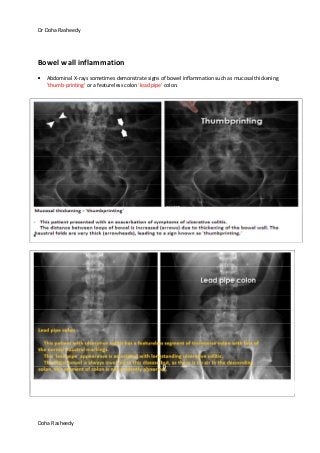

Bowel wall inflammation

Abdominal X-rays sometimes demonstrate signs of bowel inflammation such as mucosal thickening

'thumb-printing' or a featureless colon 'lead pipe' colon.

Thumb printing (bowel wall inflammation)

Findings: Mild to moderate bowel edematous walls of the tranverse colon.

Diagnosis: Crohn's Disease

Discussion:

Thumbprinting of Bowel DDx:

Inflammatory Bowel Disease - most common. i.e. Crohn's and Ulcerative Colitis

Diverticulosis or Diverticulitis

Ischemic Colitis with hemorrhage into bowel wall

Other Uncommon causes include:

Thumbprinting

(red arrows) of

ascending and

transverse colon

and featureless

bowel wall

(yellow arrow) at

the left transverse

colon extending

into splenic

flexure, consistent

with wall

thickening.

The normal diameter of the intestines on an AXR do not usually exceed:

Arrows: bowel

wall thickening

Arrow heads:

thumb printing